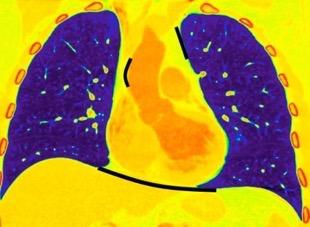

La ocupación del espacio pleural por derrame (o obstrucción aérea) se acomoda con expansión aumentada de la caja torácica, especialmente en eje vertical. La consecuencia es aplanamiento e incluso inversión diafragmática.

Afzal S, Fatima K, Ambareen M. Antenatal ultrasound diagnosis of congenital high airway obstruction syndrome: a case report and review of literature. Cureus. 2019. Thoma R et al. Physiology of breathlessness associated with pleural effusions. Curr Opin Pulm Med. 2015

Wang JS et al. Changes in pulmonary mechanics and gas exchange after thoracentesis on patients with inversion of a hemidiaphragm secondary to large pleural effusion . Chest 1995